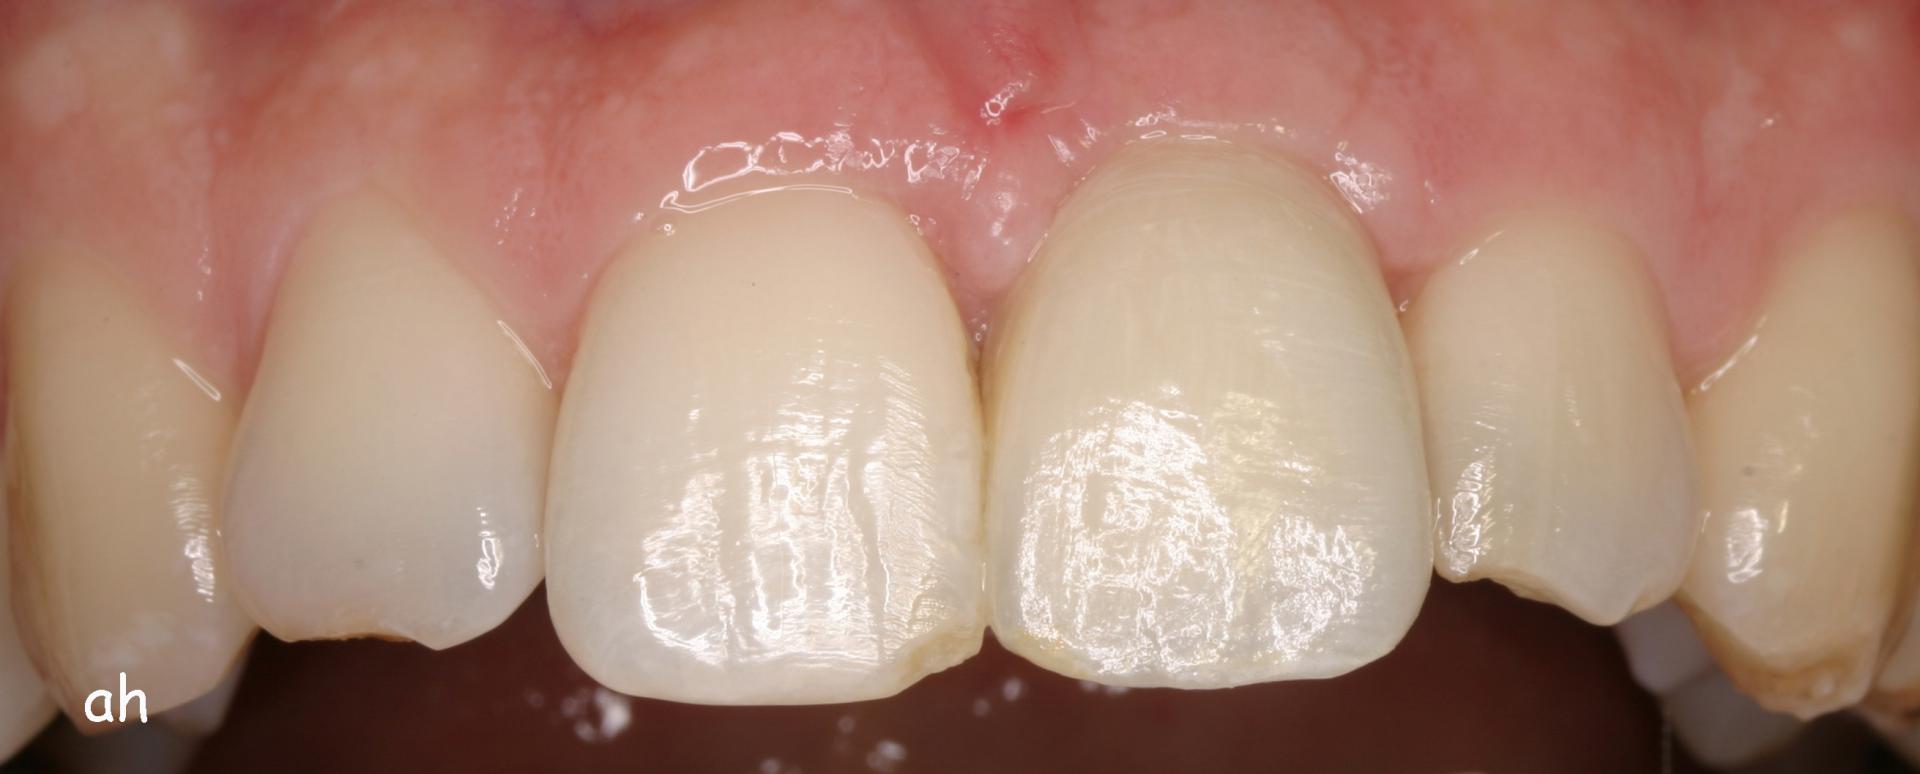

Exemple 1: Ce patient a perdu son incisive centrale gauche lors d'un accident. Un implant a été posé

Exemple 1: L'implant remplace la racine de la dent manquante

Exemple 1: L'implant s'est intégré dans l'os, une empreinte est effectuée. Le laboratoire peut réaliser la couronne en céramique.

Exemple 1: résultat final.